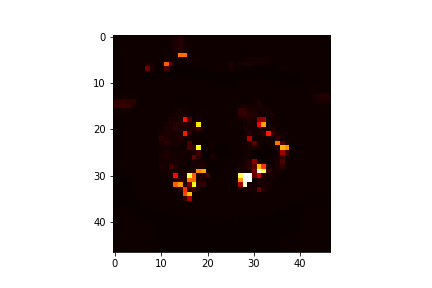

Refer to caption

Figure 6: Prediction of probability map by model.

The proposed 3D CNN architecture achieved an accuracy of 94.8% on validation data. Figure 3 shows the training accuracy and validation accuracy as the model was trained. It may be observed from the figure that the accuracy is gradually increasing during training. Figure 4 shows that the loss curve of training samples and validation samples.To improve the quality of this model, the validation loss and validation accuracy over epochs was monitored using tensorboard logs and hyper parameters were appropriately adjusted. The performance with respect to accuracy becomes stable after several iterations. This behavior is correlated with the change in loss as shown in Fig 5 which is decreasing gradually during training, and when the network obtains an optimal point then the training process becomes stable. Overall, the proposed deep 3D convolutional neural network is effective in classification as shown in fig 4 depicting the accuracy during the validation process. In order to demonstrate the performance of our model a complete CT scan containing annotated malignant nodule was sampled into multiple cubes using sliding window and subsequently fed to the trained 3D CNN network and probabilistic predictions corresponding to each input sample is plotted in 2 Dimension. Fig 6 shows the predicted probability map from the model in 2 Dimension while fig 7 shows the regions with probability greater than 90% after removal of noisy predictions .Fig 8 shows 2D slice of corresponding input sample. It may be observed that location of the annotated nodules has very high-probability but a small number of false positives are also predicted as shown in Fig 6. Evaluation of model on test data yielded a score .208 and accuracy of .9514.Due to the extensive duration of the training process hyper-parameters initial learning rate, momentum decay was adjusted only once. Further optimization of these parameters is expected to improve the quality of the model and reduce false positives.